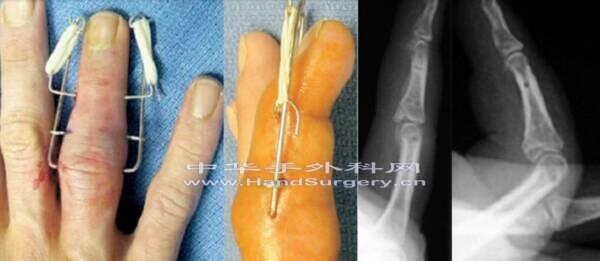

2008年,美国学者Ruland,报道在美国手外科杂志的方法